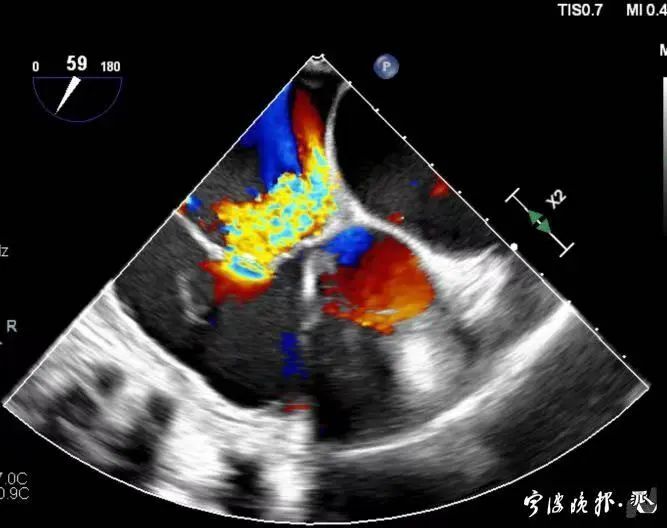

術(shù)后食道心超示三尖瓣反流消失

得知可以微創(chuàng)手術(shù),陳大爺一家決定放手一搏。寧波市醫(yī)療中心李惠利醫(yī)院心臟瓣膜中心團(tuán)隊(duì)反復(fù)就術(shù)前準(zhǔn)備、手術(shù)步驟及術(shù)后可能出現(xiàn)的各種情況做了預(yù)案。3月4日,陳大爺?shù)氖中g(shù)成功進(jìn)行,術(shù)中得到LuX-Valve經(jīng)導(dǎo)管三尖瓣置換術(shù)原創(chuàng)團(tuán)隊(duì),上海長海醫(yī)院陸方林主任團(tuán)隊(duì)的鼎力支持,術(shù)后陳大爺?shù)男呐K三尖瓣反流立即消失。術(shù)后瓣膜中心CCU(心臟監(jiān)護(hù))團(tuán)隊(duì)和心內(nèi)科團(tuán)隊(duì)迎接一個又一個右心瓣膜置換后的血流動力學(xué)改變等帶來的挑戰(zhàn),克服種種難關(guān),二周后患者進(jìn)入早期心臟康復(fù)。目前陳大爺已經(jīng)順利出院,沒有胸悶氣急,生活自理,精神狀態(tài)也很好,瓣膜中心團(tuán)隊(duì)也在對他持續(xù)隨訪中。